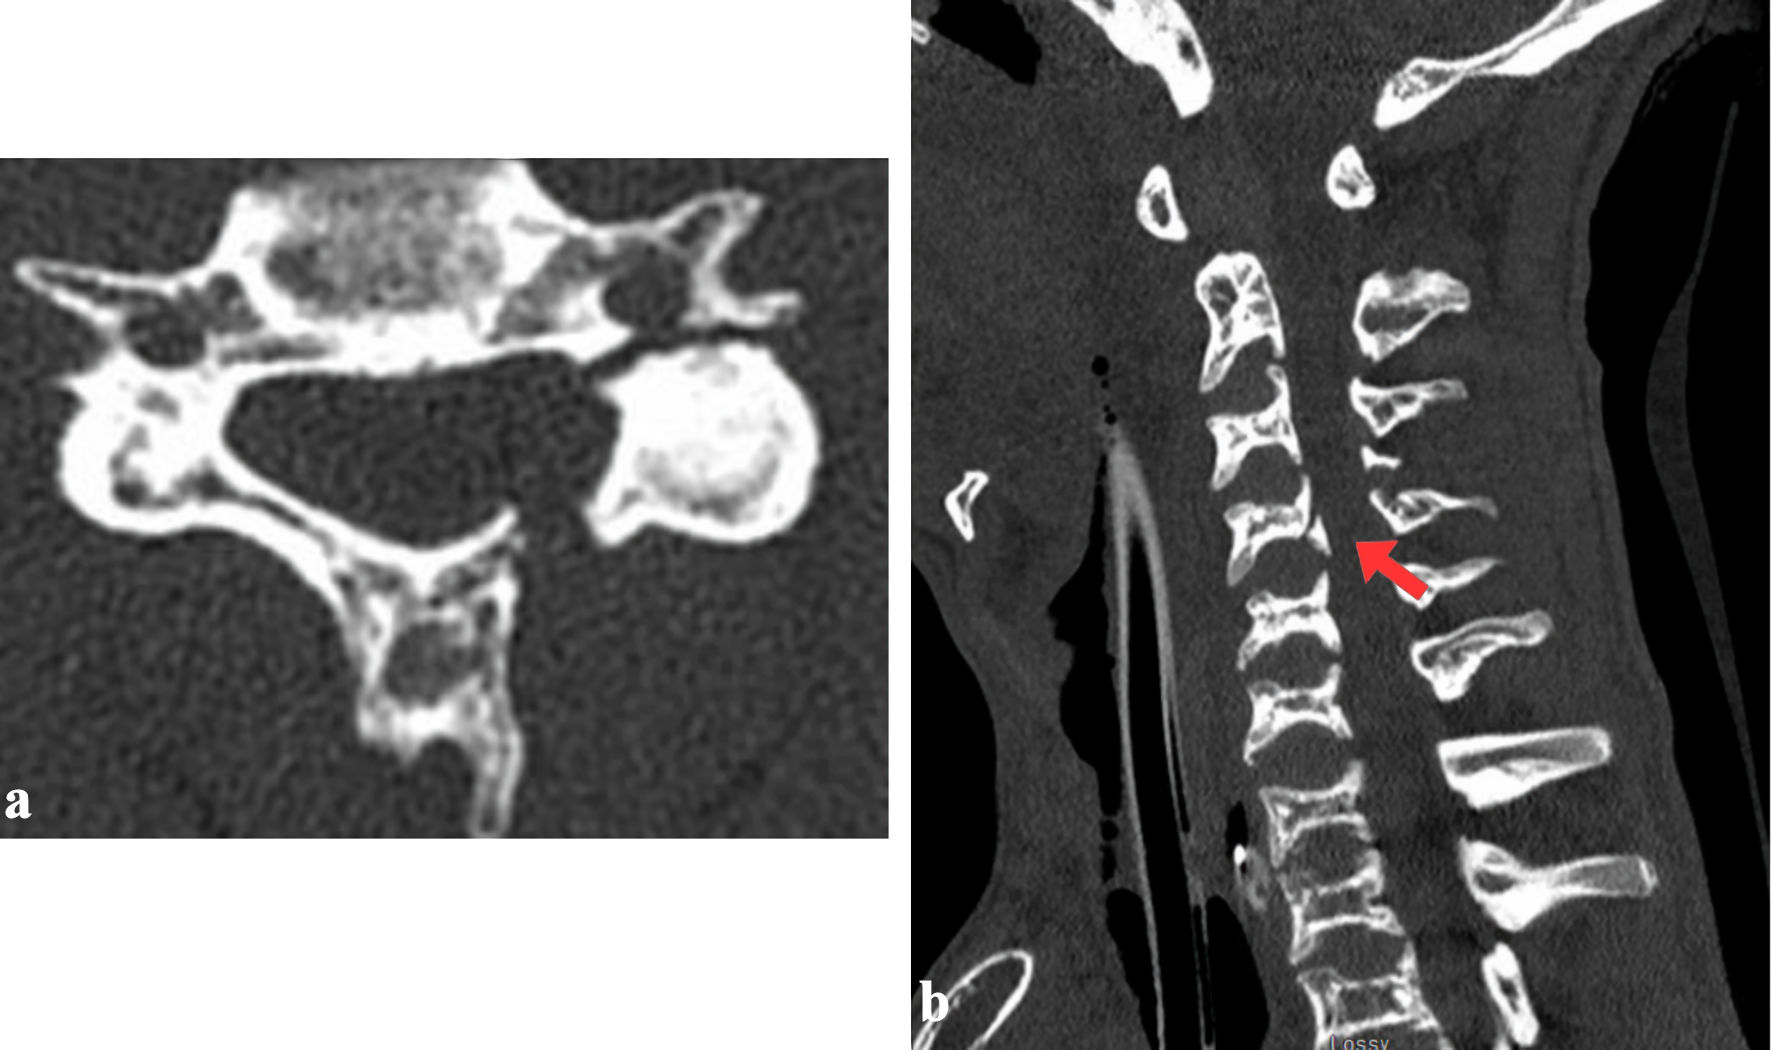

At a follow-up approximately 3 months post-injury, he remained asymptomatic with stable cervical alignment. A final dynamic flexion-extension CT of the cervical spine performed 1 year post-injury showed interval healing, with complete bone fusion of the C3 and C4 body fractures but incomplete fusion of the C4 facet and lamina (Figs. 3, 4). Alignment was stable in flexion and in extension. At his final clinical assessment, the patient remained pain-free, maintained full neurological function, and was subsequently discharged from routine neurosurgical care.

Figure 3. Radiographic follow-up at 1 year showing flexion (a), neutral (b) and extension (c) positions with no dynamic instability (red arrows).

Figure 4. Final CT at 1-year follow-up demonstrating healed C4 fracture and lateral mass alignment in axial view (a), right (a) and left (c) side (red arrows). CT: computed tomography.